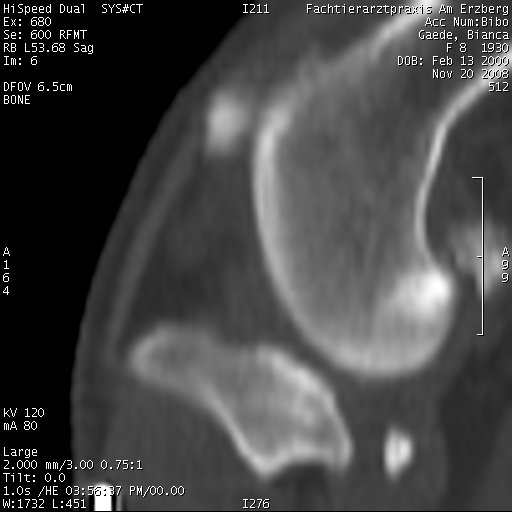

Im CT mit Kontrastmittel hat man den Riss nicht sehen können, nur die Flüssigkeitsansammlung im Knie.Persönlich, wenn es unklar ist, sprich auch der Schubladentest negativ ist, würde ich wohl eher ein MRT machen lassen, wenn die Möglichkeit besteht.

Ich finde, so wirklich erkennen kann man nicht, daß das Kreuzband gerissen ist. Klar, die Arthrose kann man sehen und mehr Flüssigkeit, aber sonst